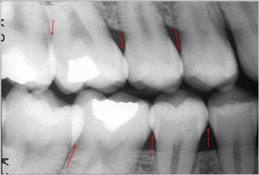

Sistema radiográfico ICDAS

(Radiografía Bite-Wing) |

Sano |

R0 |

No hay

radiolucidez |

Estadios

iniciales * |

RA1 |

Radiolucidez en

1/2 externa del esmalte |

RA2 |

Radiolucidez

en la 1/2 interna del esmalte ± UAD

(Unión amelo-dentinaria) |

Se lo considera aún un estadio

inicial porque no hay dentina

infectada ) |

RA3 |

limitada al 1/3 externo de la

dentina |

Estadio

moderado

(En este estadió

comiemza la infección de la dentina por bacterias orales) |

RB4 |

Radiolucidez que

alcanza hasta el 1/3 medio de la

severos

(Infección franca de la dentina) |

RC5 |

alcanza hasta el 1/3 interno de la

dentina, clínicamente cavitada

RC6 |

la pulpa, clínicamente cavitada

|

Tabla 4: Clasificación

radiográfica ICDAS